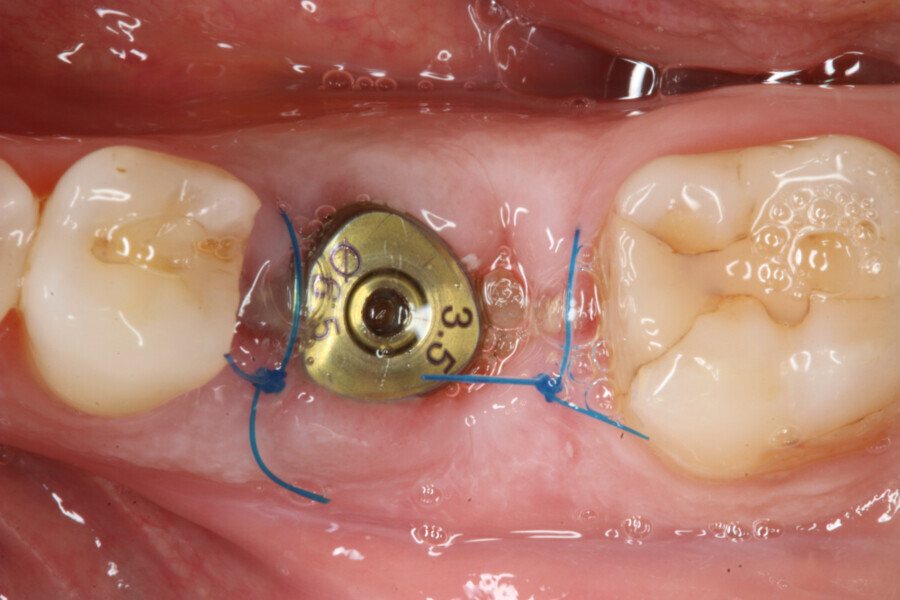

The implant site was prepared following the recommended drilling protocol for the planned PrimeTaper EV 4.2 mm diameter implant (drills #1, 3 and 4; Fig. 2). After cortical preparation with drill #5, the implant was placed. The preparation was finalised with a tap, owing to dense trabecular bone (Fig. 3). The implant was inserted to a torque of 42 Ncm (Fig. 4).

Immediately after implant placement (Fig. 5), the abutment position was registered with an intra-oral scan using Primescan (Dentsply Sirona; Fig. 6). At the end of the surgical procedure, the socket was grafted with Symbios (Dentsply Sirona) and a healing abutment was seated (Fig. 7). Radiographic evaluation was performed on the same day (Fig. 8). On basis of an intra-oral scan, an Atlantis abutment and Atlantis provisional crown were designed and fabricated with an Atlantis IO FLO (Fig. 9).